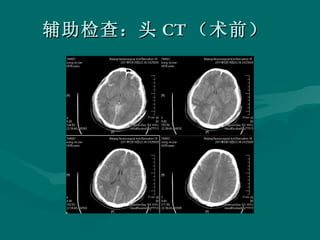

病例 男性, 35 岁,因头外伤后昏迷伴右外耳道及鼻孔出血 4 小时急诊以急性颅脑损伤收入院。入院查体:患者中度昏迷, GCS7 分,双瞳等大等圆,左:右 =3 : 3 ,光反应灵敏

辅助检查:头 CT (术前)